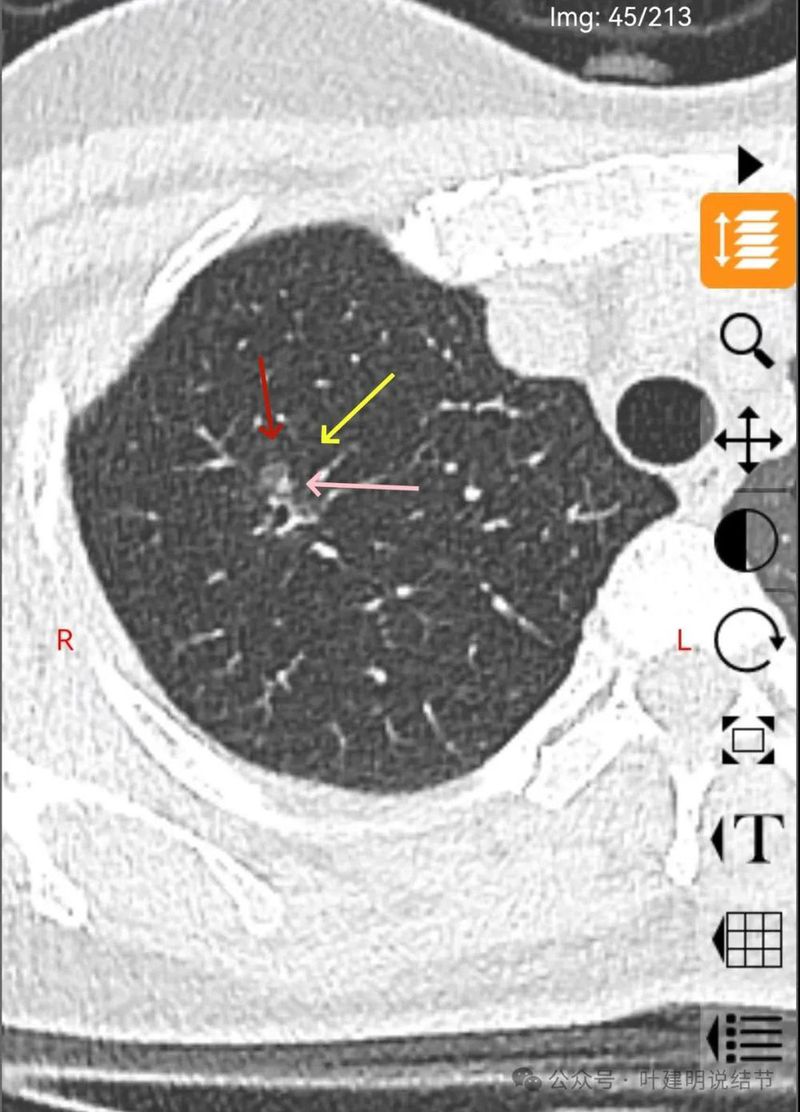

有实性成分出现。

形态不规则、轮廓与边界清、多支血管进入穿行、支气管扩张,表面不平。

磨玻璃密度伴灶内支气管扩张。

支气管扩张,病灶磨玻璃密度,有血管进入穿行。